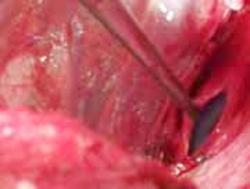

Sindrom de compartiment Sindrom de compartimen

Fasciotomie mediala superficiala Fasciotomie mediala

Sindrom de compartiment Plaga impuscata in regiunea poplitee

Fasciotomie laterala